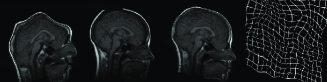

In Figure 9, three example registration results of randomly and nonlinearly warped images are shown. Capturing signal intensity variations during registration process with intensity standardization method leads to assesment of visual comparision of registered source and target images with warping grid. Evaluation of the registration results is summarized in Table-2. The table shows that large and small scale deformations are captured accurately on the standard intensity scale. Resulting images have fixed intensity meanings even there is large intensity variations initially.

The resulting registered images and deformation fields show that standardization of intensity scales improves the accuracy of registration.